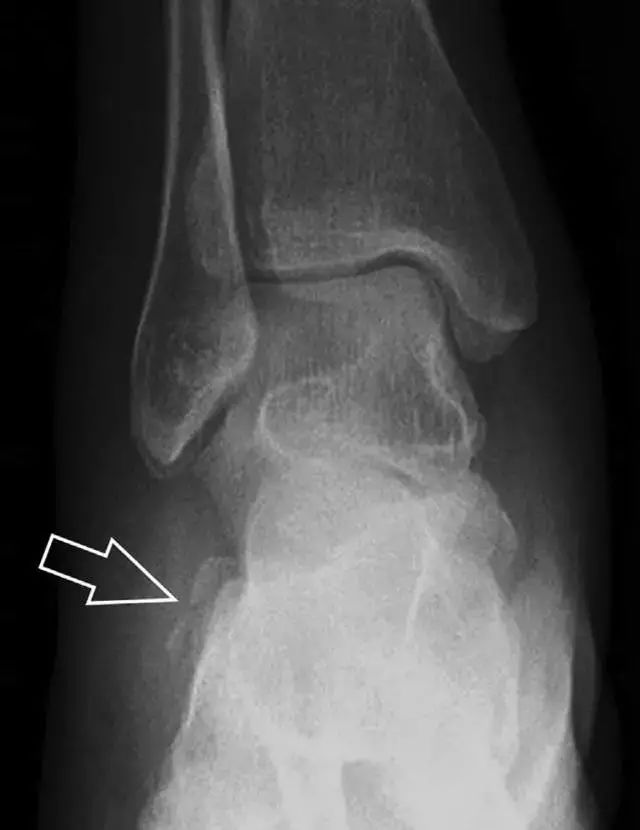

距骨后突骨折

距骨后突有内侧结节和外侧结节,距骨后突内侧结节撕脱性骨折常发生在背屈内旋的*力暴**作用下。严重跖屈时,胫骨后缘和跟骨挤压距骨后突外侧结节呈楔形,易发生粉碎性骨折。这些骨折细微且需与三角骨鉴别。侧位片观察距骨后突骨折最佳,常规拍片很难发现,当高度怀疑这种骨折又没法做 CT 时,建议加做多个角度的外旋斜位片(图 5)。

图 5 距骨后突骨折。侧位片(A)和 MRI 矢状位 T1 加权像(B)均示后外侧突的简单骨折(箭头),再次阅片时才发现 X 线片上的骨折;侧位片(C)和 CT 横断面图像示后内侧突的粉碎型骨折(箭头)。